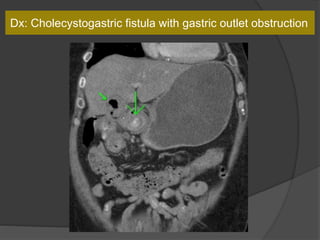

Case 5: 64 M with abdominal pain and vomiting

Dx: Cholecystogastric fistula with gastric outlet obstruction

Gastric outlet obstruction caused by a large gallstone

passing into the duodenal bulb through a biliogastric or

bilioduodenal fistula.

What is it called?

Bouveret's syndrome